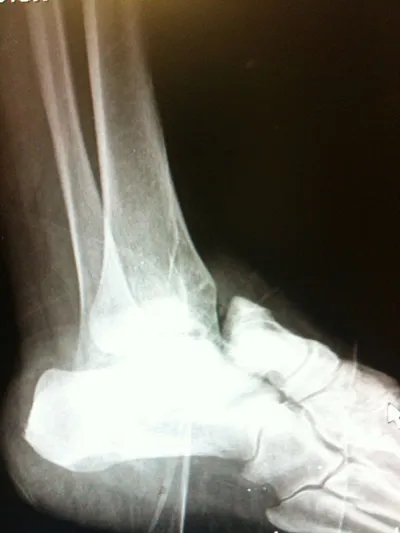

Pictures of a talar neck fracture with displacement of the talar body and subtalar and ankle dislocation prior to surgery